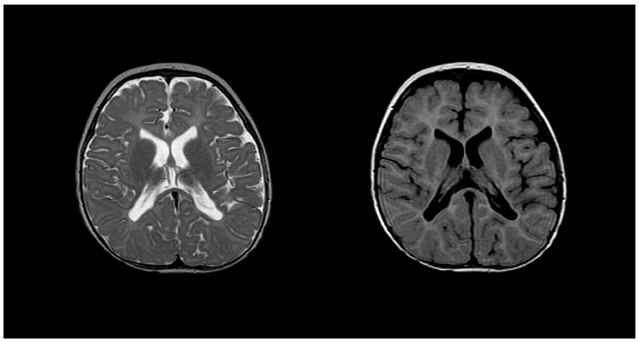

• MRI 特征:内囊、放射冠、视辐射区髓鞘缺失,T1 低信号、T2 弥漫高信号。

佩梅病患者的 T2(左)与 T1(右)MRI 图像显示内囊、近侧放射冠及视辐射区域髓鞘发育缺失。